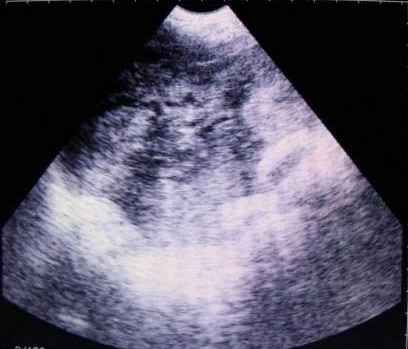

獸用B超機檢測母豬空懷圖像